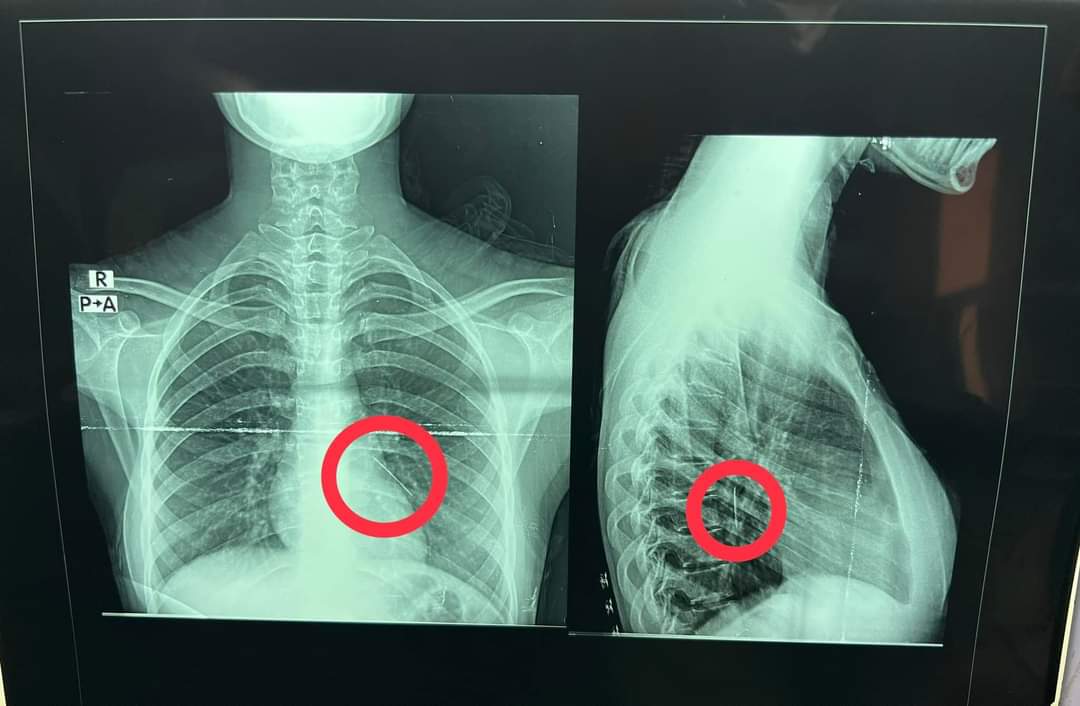

نجح فريق جراحى بقسم جراحة القلب والصدر بمستشفى بنها الجامعي بمحافظة القليوبية، في إنقاذ حياة فتاة تبلغ من العمر حوالي 18 سنة، ابتلعت دبوس طرحة عن طريق الخطأ أثناء لبسها الطرحة حيث استقر بالرئة، وتم إجراء جراحة منظار شعب هوائية لها واستخراج الدبوس دون الحاجة لفتح صدر المريضة.

وأشار مستشفى بنها الجامعي بمحافظة القليوبية، بقيادة الدكتور عمرو الدخاخني المدير التنفيذي لمستشفى بنها الجامعي في بيان إلى أنه تم إجراء عملية طارئة لاستخراج دبوس طرحة من القصبة الهوائية اليسرى لفتاة تبلغ من العمر 18 عاما، ابتلعته عن طريق الخطأ أثناء لبسها للطرحة ونزل في الرئة.

وأوضح الدكتور محمد الجزار استشاري جراحة القلب والصدر بالمستشفى، أنه تم على الفور إدخال الفتاة لقسم جراحة القلب والصدر، وتم إجراء عملية منظار شعب هوائية صلب، وتم استخراج الدبوس دون الحاجة لفتح صدر المريضة.